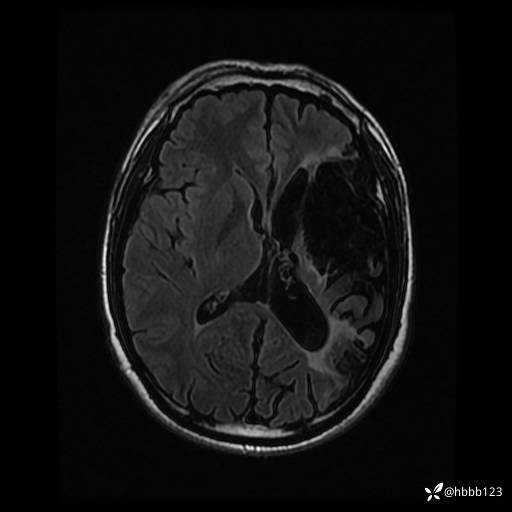

患者男,43岁。

简要病史:癫痫患者复诊,昨日发作5-6次,建议住院进一步治疗。

入院完善脑癫痫组合序列:

T2 Flair: